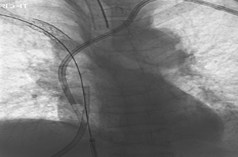

Balloon Dilatation